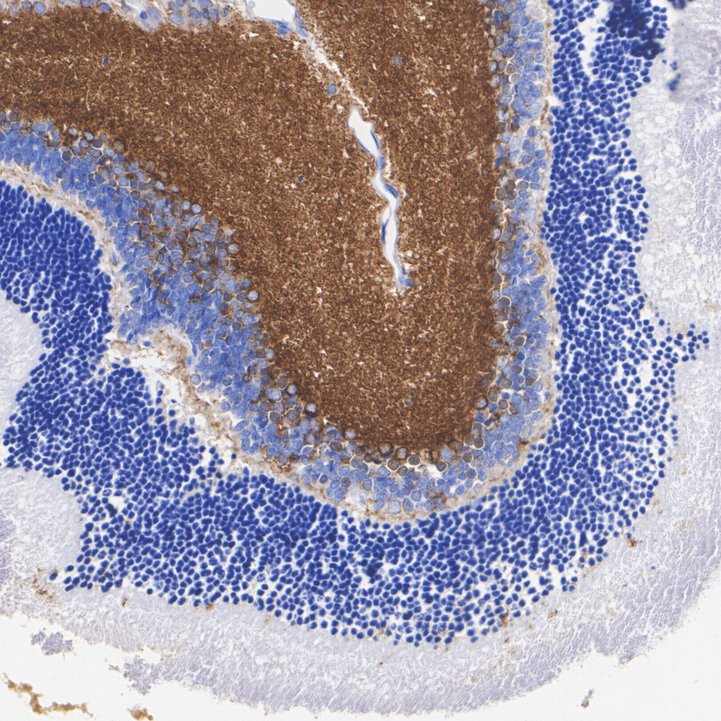

Synapsin I + II Recombinant Rabbit Monoclonal Antibody [PSH10-29]

IHC-P